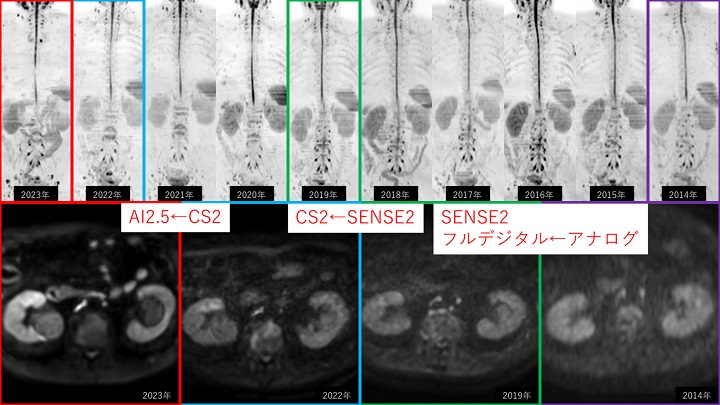

体幹部を中心にの SmartSpeed AI の新たな臨床応用についてご発表いただきました。10 年以上の Philips MRI の使用経験をもとに、デジタルからアナログ、SENSEI→CS→AI の高画質化・時間短縮の歴史を振り返って紹介いただきました。現在、臨床では SmartSpeed AI を超高速化モード、超高分解能モード、その両方など、様々な応用パターンで使用いただいております。乳腺の Ultra-fast dynamic や超高分解能な造影後 Dixon、EOB のダイナミックでのアーチファクト対策など、新たな応用方法を試みを紹介いただきました。

特に腹部 DWI の 2.5mm Isotropic DWI に AI (W.I.P)を併用したデータを提示いただき、薄いスライスでも高い SNR を担保して撮像することで ADC の精度が向上することを示していただきました。